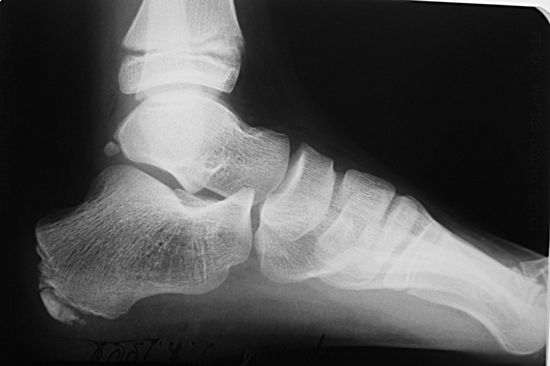

Розвиток хвороби Шинца можна визначити по скаргах дитини і під час зовнішнього огляду. Лікар-ортопед проводить діагностику, спираючись на результат рентгенівського знімка, щоб зрозуміти складність захворювання і призначити правильне лікування. В хірургії зустрічаються захворювання, які схожі на недугу Шинца, тому потрібно бути гранично обережними при постановці діагнозу. Подібна симптоматика спостерігається у таких хвороб, як: